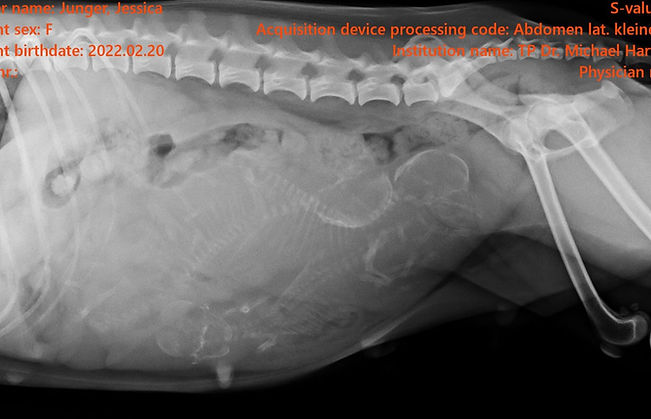

Röntgen

Das Röntgen ist wichtig um unter der Geburt frühzeitig erkennen zu können, wann Hilfe nötig wird.

Dieses Mal zeigt das Röntgenbild 3 Welpen.